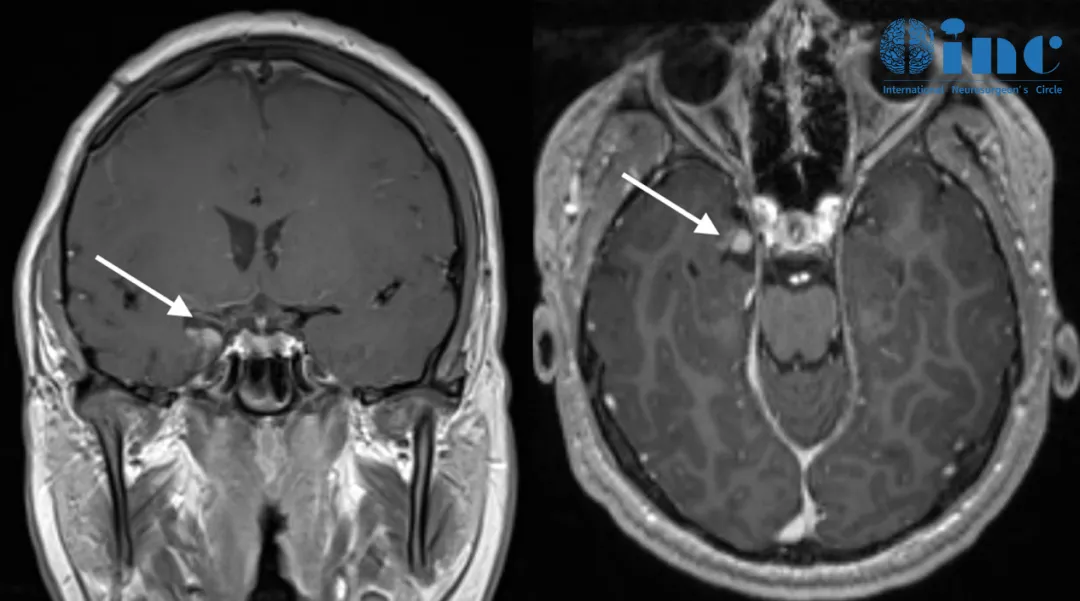

手术七年后复发影像

在手术切除后,Jimmy享受了七年的宁静时光,但在他14岁那年癫痫再次发作,检查发现他的内侧颞叶肿瘤出现了小的残留病变,周围可能也是致痫灶,这些导致了癫痫复发,如不及时治疗,可能会逐渐回到术前状态,再次陷入癫痫的“梦魇”,但Jimmy这次不愿再次接受开颅手术,他希望能尽快完成治疗重返校园。

一家人找到国际儿童脑瘤教授INC Rutka教授,Rutka教授与Jimmy及其家属进行了深入沟通,教授认为Jimmy的残余肿瘤不足3cm,适合采用一项微创技术——激光间质热疗(LITT)来消融病变。教授表示术后Jimmy可以很快出院,不会影响正常的学习和生活,与Jimmy一家达成共识后,教授立即为其制定了周详的微创治疗方案。由于Rutka教授团队对于整个LITT技术已经有丰富的经验,Jimmy的手术很成功。